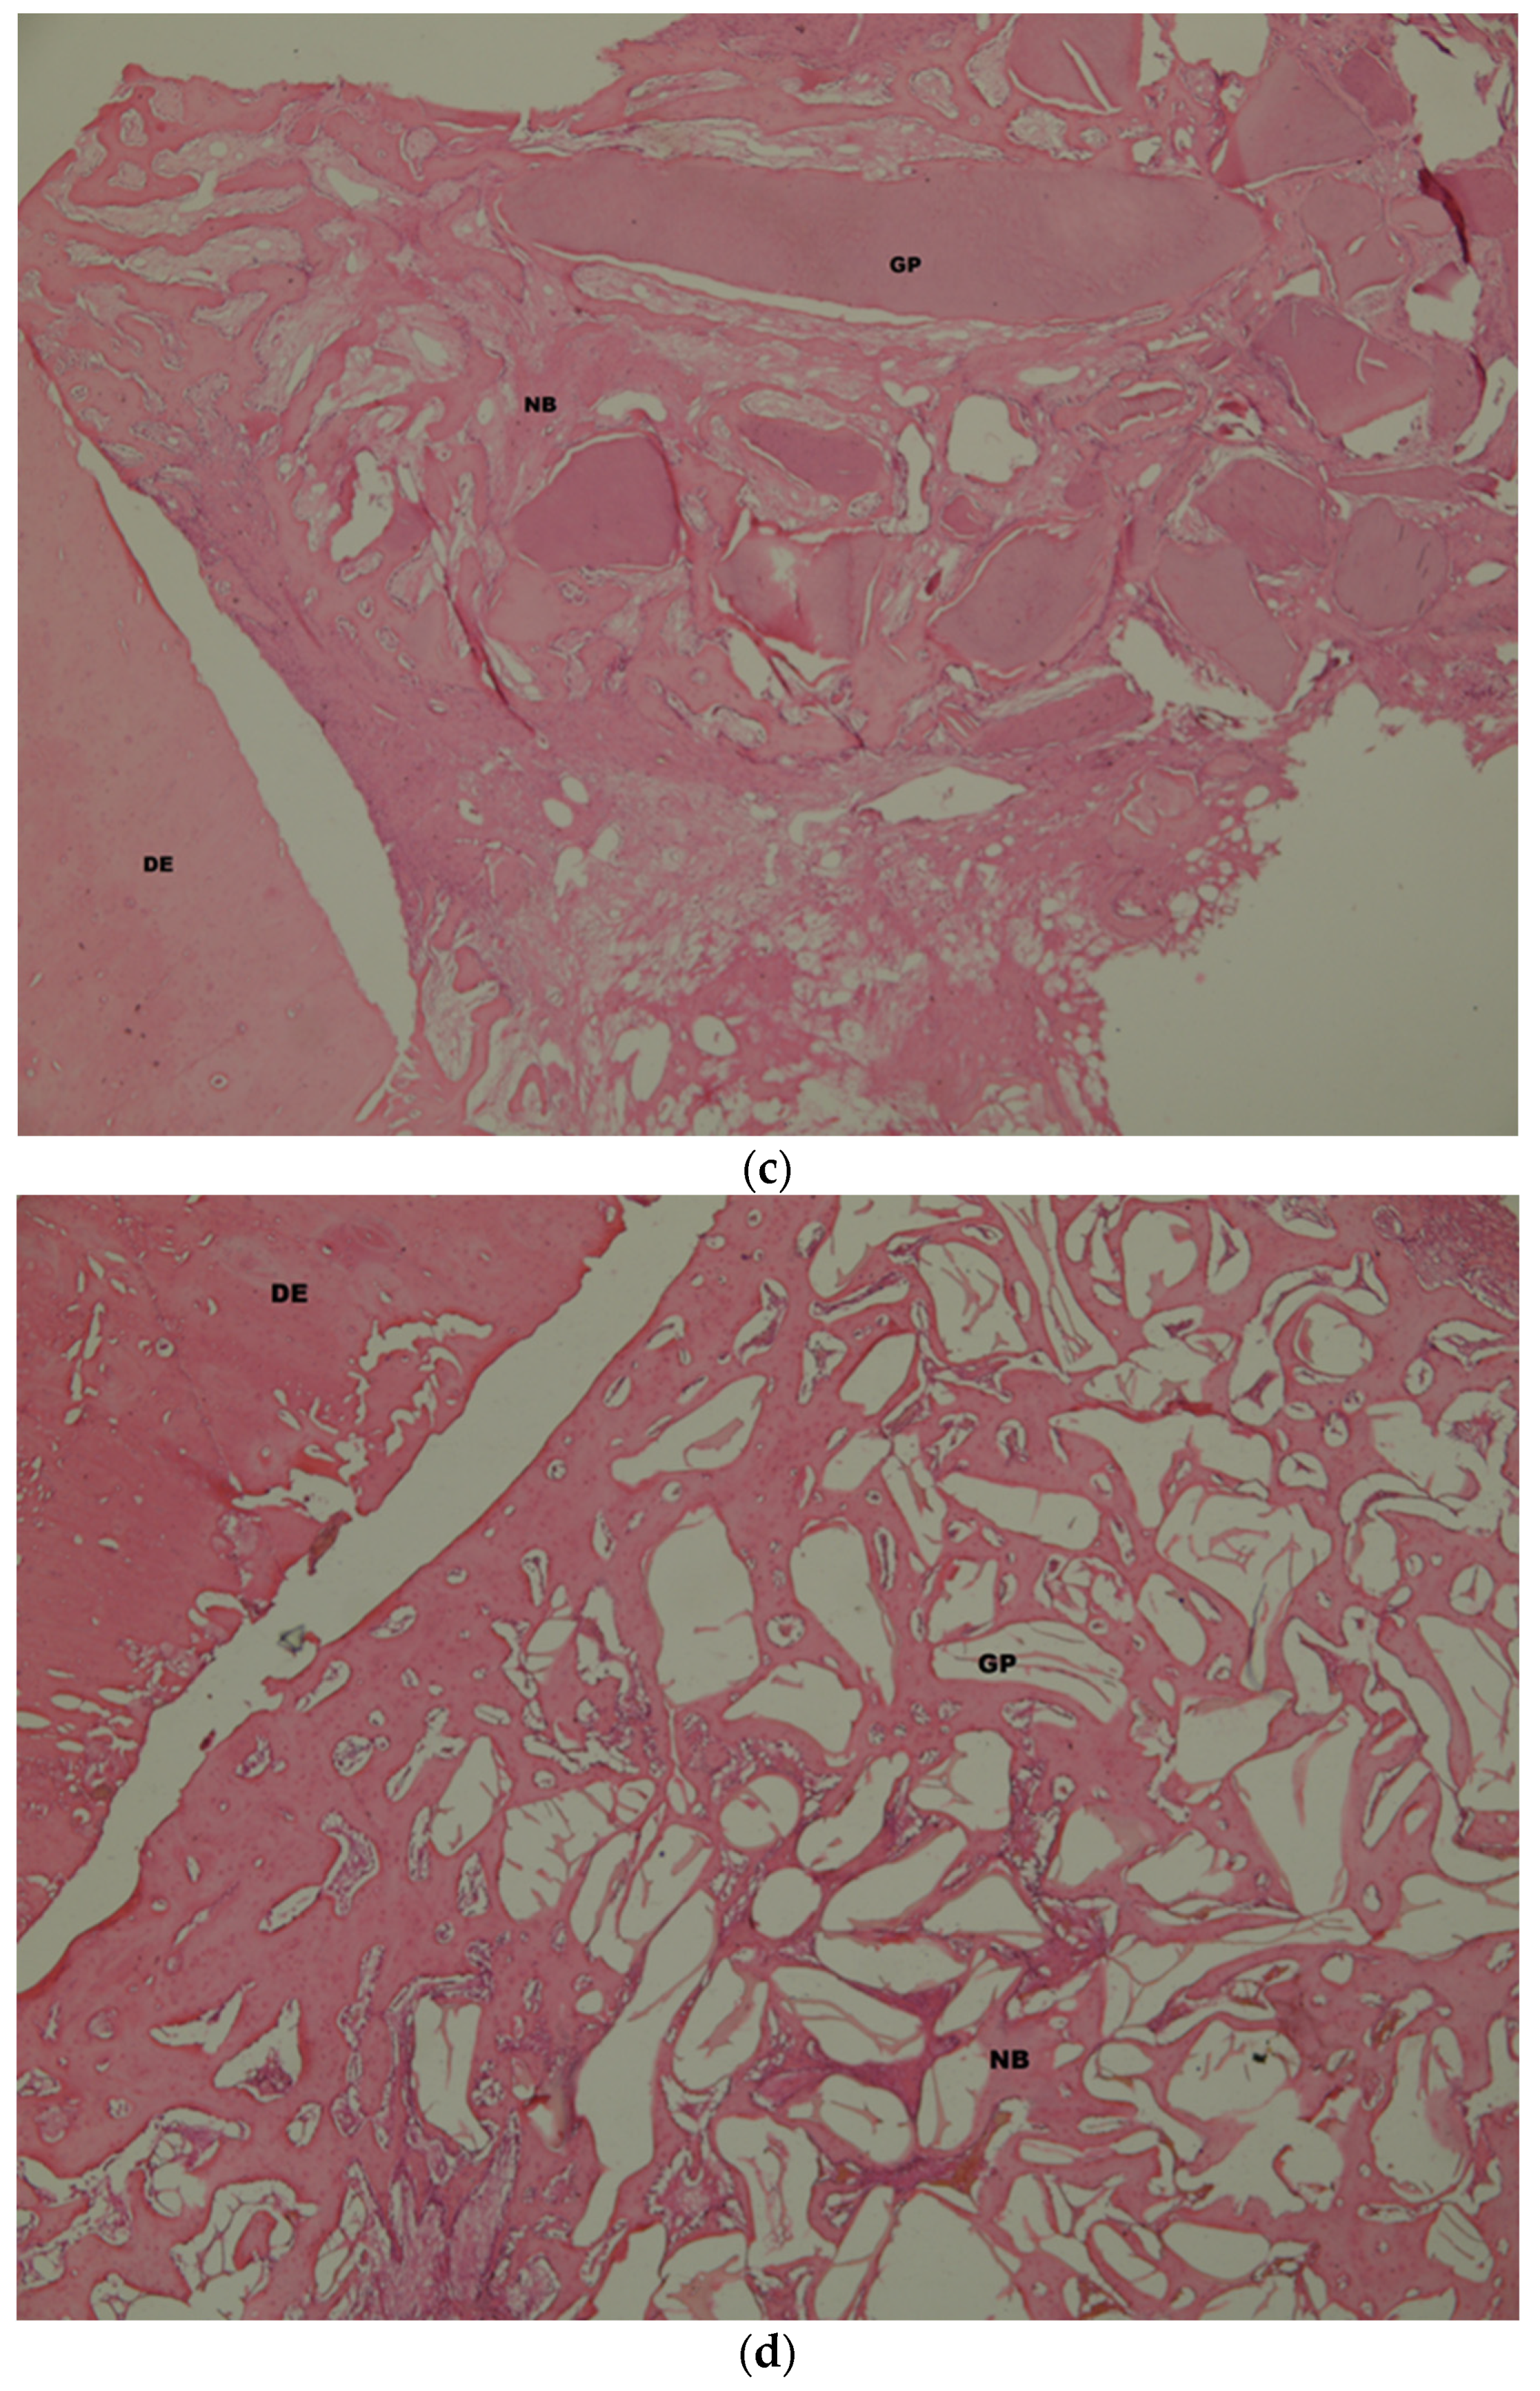

3.2. Histologic and Histomorphometric Findings